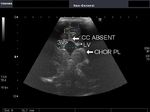

AGENESIS OF THE CORPUS CALLOSUM in AICARDI SYNDROME

This young female neonate presented with infantile spasms and anophthalmia. Sonography of the brain revealed a) absence of the corpus callosum b) prominent, dilated and elevated 3rd ventricle c) sharply angled lateral peaks of the lateral ventricles which lie far apart d) colpocephaly- prominence of the occipital horns of the lateral ventricles e) echogenic mass in the medial part of the lateral ventricles (Probst bundles) f) posterior fossa cyst which communicates with the dilated 4th ventricle with agenesis of the cerebellar vermis (DANDY WALKER MALFORMATION). These ultrasound images suggest agenesis of the corpus callosum, as part of the AICARDI syndrome. Ultrasound images by Joe Antony, MD, using a Toshiba Xario ultrasound machine.